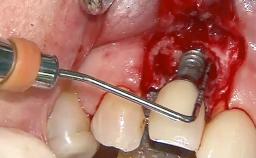

Treatment of Peri-Implantitis at a Zirconia Implant

Due to their promising clinical performance, zirconia implants have recently become popular alternatives to titanium implants, particularly for areas with high esthetic demands (Holländer and coworkers 2016; Roehling and coworkers 2016; Lorenz and coworkers 2019). However, regardless of the reported high survival and success rates, zirconia implants were affected by peri-implant diseases over the short observation period, suggesting the importance of treating peri-implant diseases at zirconia implants (Becker and coworkers 2017). In their case, Frank Schwarz and Ausra Ramanauskaite present 3-year results following mechanical debridement alongside Er:YAG laser monotherapy.